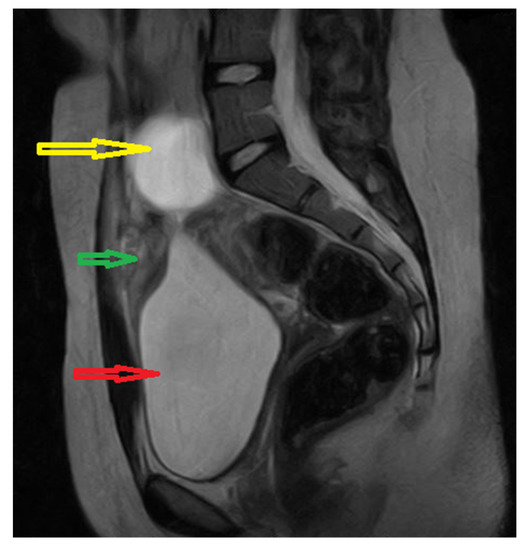

Because the radiologists requested additional investigations, an abdominal–pelvic CT scan with intravenous contrast was performed, adding an intense contrast capture in the periphery of the lesion with edema of the prevesical space (Figure 2 and Figure 3).

Figure 3. Axial CT scan of abdomen and pelvis with intravenous and oralcontrast: red arrow; supposed urachal cyst; yellow arrow: urinary bladder;green arrow: uterus; blue arrow: left ovarian cyst.